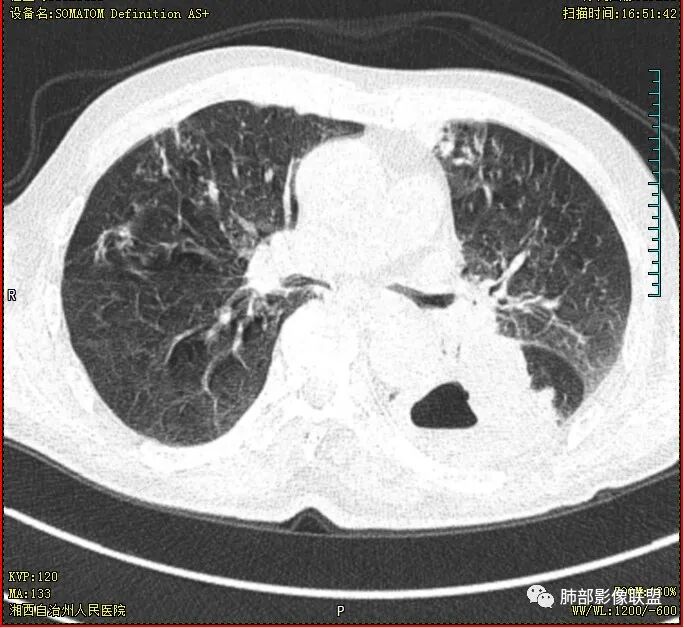

晨读 双肺多发斑片、斑点影,可见树芽征,支气管播散,右肺上叶小空洞,左肺下叶厚壁空洞,内壁较光整,有浅液平,右下叶背段支气管变窄,不均匀强化。结合临床考虑结核并感染,待排除合并肺癌可能。

晨读:老年男性患者,痰中带血伴间断发热2周,体温39.4℃,白细胞、中性粒细胞,CRP增高,Tspot阳性,胸部CT:双肺病变,左肺下叶背段大片实变密度影,边界模糊,内部见空洞形成,空洞内壁总体光滑,有气液平,增强扫描轻度不均匀强化,一月后复查空洞消失,实变影吸收减少,考虑感染性病变,结核伴肺脓肿。

晨读,老年男性,中等病程,咳嗽,痰中带血,发热,主病灶位于左肺下叶空洞,厚壁,偏心,内壁光滑,边界清楚,不均匀强化,内有坏死,考虑结核,内有气液平,周围部分小叶中心结界,好热,白细胞升高,合并感染。结核合并感染,鉴别肺癌合并感染。

老年慢性长期吸烟,痰中带血伴发高热。左下肺大片不均质实变里可见一含气液平厚壁空洞,内壁有坏死物残留,增强可空洞壁明显强化轮廓显示清晰,空洞位于肺门侧,近端支气管壁不规则增厚。两肺散在斑片状影,并见小树芽。18号复查肺窗空洞显示不清,20号用了俯卧位扫描,液体向下流动空洞又显示出来了。左下肺病灶有变小,还是考虑感染性病变,结核合并感染,鉴别鳞癌。

双肺多发结节影,树芽征,小叶中心分布,左肺下叶不规则空洞,洞内壁光滑,见液平,洞壁似与支气管相通,增强扫描明显强化,可见血管造影征。三周左右复查空洞明显缩小。

双肺多发点片、索条斑条灶,见多发树丫征,左下肺大片不均质实变,内见一含气液平厚壁空洞,壁厚,内壁有坏死物残留,增强可空洞壁明显强化

,空洞位于肺门侧,近端支气管壁不规则增厚。

胸部CT:双肺多发小斑片、树芽、索条灶,左下肺大片不均质实变,远肺门侧厚壁空洞,气液平,内壁有坏死物残留,增强可空洞壁不均匀强化,近端支气管壁不规则增厚堵塞,实变影内可见与洞壁平行支气管。抗炎3周有缩小。

3.注意到左肺下叶空洞性病灶,腔壁厚度不均,环形强化较为明显,壁间支气管血管影走行,腔内液气平面,这通常见于感染性病灶,如脓肿,经治疗病灶吸收也高度支持病灶主体成分为脓肿。